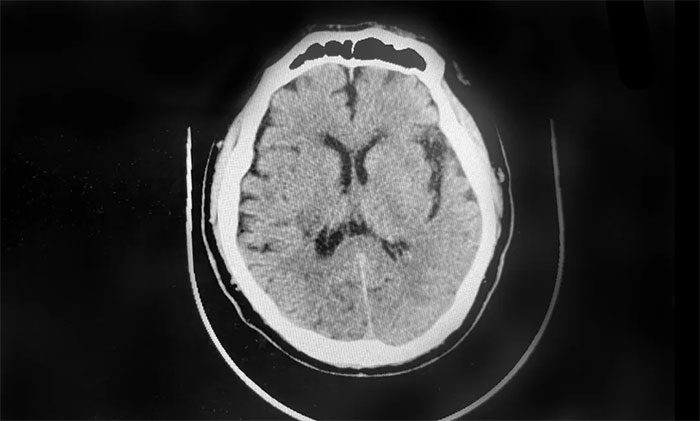

▲ 經(jīng)治療,血腫逐漸吸收

肺炎是腦出血常見兇險的并發(fā)癥,嚴重者可致命。李振并主任、孔祥玉醫(yī)生立即為其開展了系統(tǒng)的抗感染治療,李蘭馨護士長帶領(lǐng)的護理團隊則對患者加強護理,密切關(guān)注患者體征變化。悉心專業(yè)的治療和護理,很快幫助徐老伯度過了難關(guān),也為患者康復(fù)打下了堅實的基礎(chǔ)。